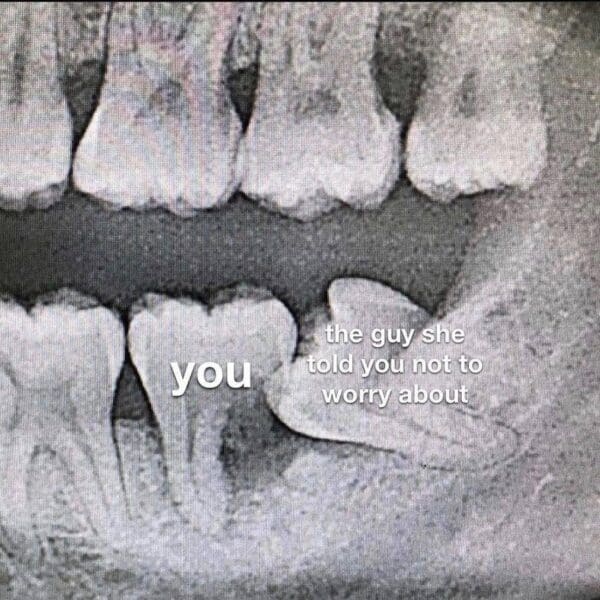

Dentists are the only people who ask you questions while they hold your tongue hostage. Respect. This gallery honors dentist memes, the jokes that sparkle like enamel and sting like cold water on a cavity. Somewhere in this scroll I will use dentist memes exactly once and you will taste bubblegum fluoride. The fun is the ritual. We show up, lie about flossing, and leave with a tiny bag that says see you in six months which we translate as whenever my tooth becomes a percussion instrument. If you are the type who brushes like a champion the week before the visit, this is your mirror. We celebrate hygienists with forearms of steel and the brave souls who invented the ultrasonic scare machine. Laugh, rinse, repeat.

Expect dental memes for the brave, tooth memes that bite back, and flossing memes that remember every excuse. There are appointment reminders we ghost, bib clips that feel like symbolism, and sunglasses that suggest witness protection.

Medical dread turns silly fast, which is why dental memes, tooth memes, and flossing memes circulate. The images are instantly relatable, the chair, the light, the tiny pick that always finds guilt. The best posts punch up at the anxiety, not the clinicians, and they leave you with a plan. If one meme made you put floss on the counter tonight, you just upgraded your future self.